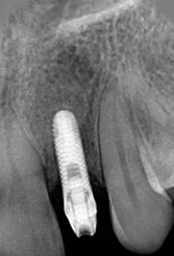

X-ray of Implant

Single Tooth Implant

X-ray of Implant + Abutment

X-ray of Implant +

Abutment + Prosthesis